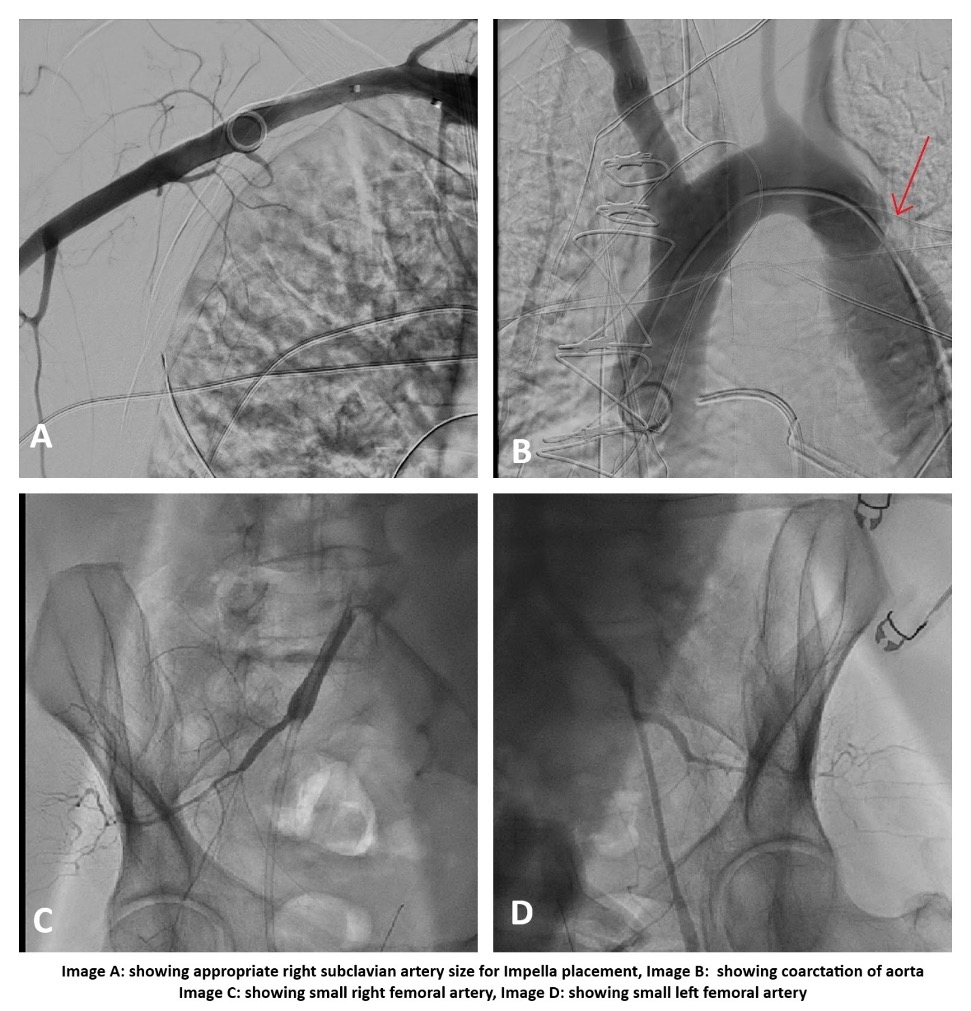

Successful Right Subclavian Impella Placement in a Patient with Coarctation of the Aorta and Small Femoral Arteries: A Novel Access Approach for Mechanical Circulatory Support

A 64-year-old male with a complex medical history, including mitral valve regurgitation/stenosis, severe aortic stenosis, mild coronary artery disease (CAD), coarctation of the aorta (diagnosed via pre-operative CT), pulmonary hypertension, patent foramen ovale (PFO), and chronic obstructive pulmonary disease (COPD), was admitted for elective surgical aortic valve replacement, mitral valve repair, and PFO closure. During surgery, the patient developed vasogenic shock requiring multiple vasopressors and inotropes. Despite placement of an intra-aortic balloon pump (IABP), the patient's condition continued to deteriorate, and he was transferred to the cardiac catheterization lab for coronary angiography and Impella support. The left femoral artery was accessed under ultrasound and fluoroscopy, but angiography revealed inadequate vessel caliber for a 14 Fr sheath. The right iliac artery was also too small. Due to aortic coarctation just distal to the left subclavian artery, this access site was excluded. Angiography of the right subclavian artery revealed suitable anatomy, so a pigtail catheter was advanced into the right subclavian artery. A 6 Fr sheath was inserted, and two pre-close sutures were deployed. An Amplatz Super Stiff wire was advanced in the ascending aorta, followed by successful insertion of a 14 Fr Impella sheath. A pigtail catheter was advanced into the LV apex, over which the 0.018-inch Impella wire was placed. The Impella CP device was then positioned, achieving flow of 3.5–3.8 L/min. The IABP and femoral sheath were removed. Coronary angiogram revealed only mild, non-obstructive CAD. The patient was transferred to the cardiac ICU in stable condition.

The Impella device is typically placed via transfemoral access. In patients with small-caliber femoral arteries or complex aortic anatomy, alternative routes must be considered. In this patient, coarctation of the aorta distal to the left subclavian artery and inadequate femoral access precluded traditional insertion sites. Right subclavian access was successfully used for Impella CP placement, with favorable hemodynamic support and outcome. To our knowledge, this is the first reported case of right subclavian Impella placement in a patient with both aortic coarctation and small femoral arteries. This case highlights the feasibility and safety of using the right subclavian artery as an alternative access route in selected patients with complex vascular anatomy.